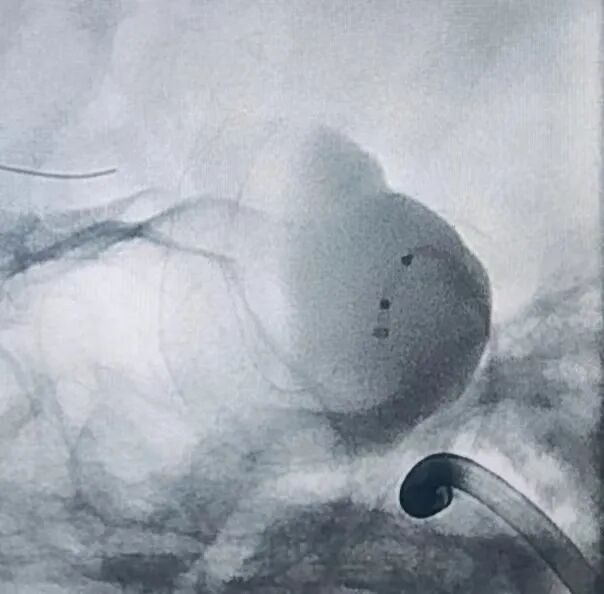

1、以Seldinger技术穿刺右侧股动脉成功后,留置6F股动脉鞘。6F DA导管超选至右侧颈内动脉海绵窦段,行3D造影提示:右侧颈内动脉床突段分叶状动脉瘤,载瘤动脉无严重迂曲,未见合并载瘤动脉严重狭窄,未见严重的脑血管痉挛。2、选择最佳工作角度,路图下用微导丝辅助支架0.027"微导管超选至右侧大脑中动脉,通过支架微导管释放一枚5.0*35mm抗凝血流导向密网支架(纽创医疗)。3、抗凝血流导向密网支架放置合适位置,完全覆盖瘤颈,释放后抗凝血流导向密网支架打开良好。术后造影见动脉瘤瘤体造影剂滞留明显,动脉瘤瘤颈造影剂滞留明显,靶动脉瘤Raymond Ⅲ级。